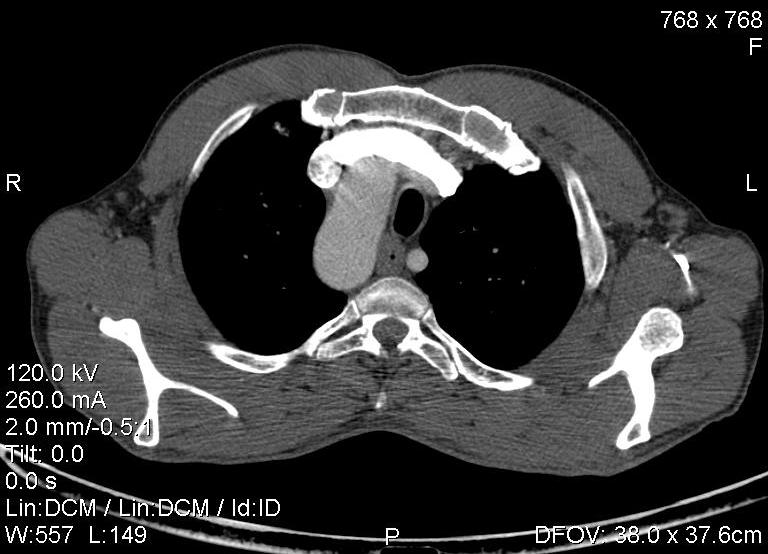

Пациент был направлен на КТ после рентгенографии ОГК, с направительным диагнозом: объёмное образование верхнего средостения.

это аномально расположенная грудная аорта

Конечно, дуга аорты идёт справа от позвоночника (декстра позиция); но есть и ещё одна аномалия той же группы: